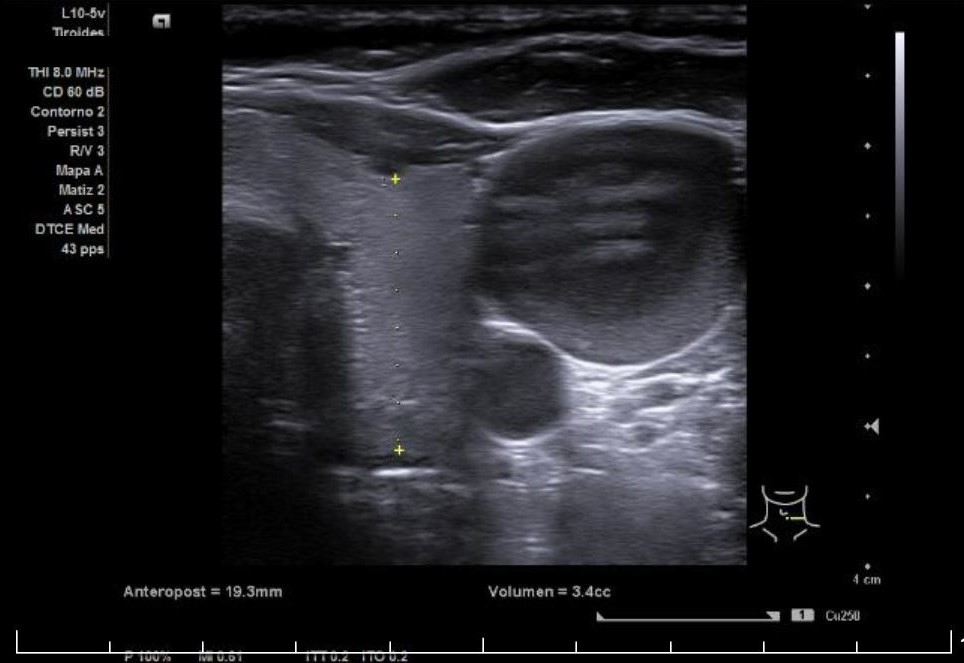

Paciente mujer de 63 años con antecedente personal de tiroiditis de Hashimoto y aumento de la grasa peritiroidea derecha que acude a consulta de su médico de familia por notarse aumento de volumen cervical anterior derecho de alrededor de una semana de evolución, negando dolor u otra clínica. A la exploración se palpa bocio ya conocido, con aumento de volumen cervical anterior derecho respecto de izquierdo, sin distinguir masa clara a la palpación. Es por la falta de claridad en la palpación que se decide realizar ecografía exploratoria durante el mismo acto clínico.

Descripción de los hallazgos ecográficos y las imágenes más relevantes para la resolución del caso

Se aprecia un tiroides de características ecográficas compatibles con tiroiditis, sin cambios respecto a ecografía previa, al igual que la grasa peritiroidea derecha, pero de manera incidental se observa un aumento del calibre fusiforme de la yugular externa derecha con respecto a la izquierda, con flujo vascular reducido.